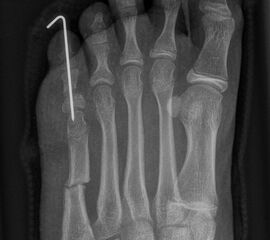

Abb. 2 a-c: offene Wachstumsfugen MT I Basis und Zehen (a), teilweise geöffnete Wachstumsfugen (b) und geschlossene Wachstumsfugen (c).

Abb. 3 a-j: Beispiel einer Calcaneusverschiebeosteotomie mit offenen Wachstumsfugen und der entsprechenden Osteosynthese mit Kirschner Drähten. Lokalisation der Osteotomie (a), Lage der Fräse (b-d), Drahtlage mehrere Ansichten (e-h), Heilung der Osteotomie 4 Wochen postoperativ und Entfernung der Drähte (i-j).